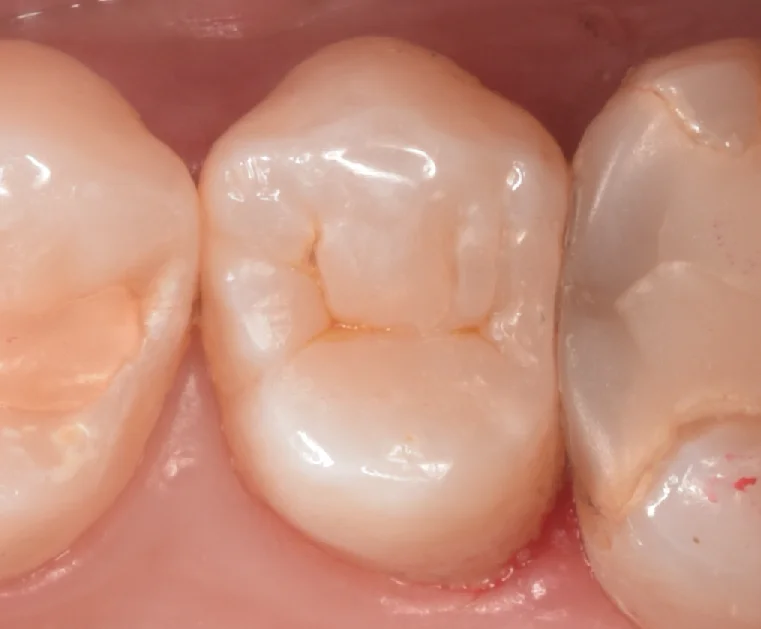

詰め終わったのがこちらになります。

歯の色・形態特に違和感なく仕上げられたかと思います。

隣の歯と相当に詰まっているタイプの歯なので、難易度は高かったですが、綺麗に仕上げられてよかったです。

斜めからも撮影させてもらったのがこちらになります。

詰めたところと歯との間に段差がなく綺麗に詰められているのがわかるかと思います。

術前術後です。

非常に難易度が高かったですが、いい仕上がりになってよかったです!